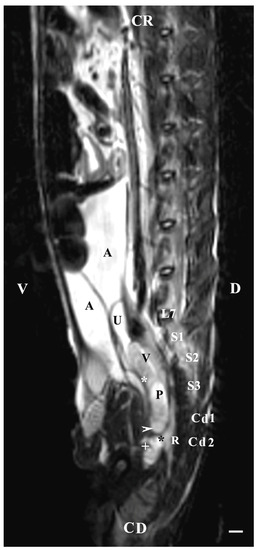

On the sagittal imaging of bulbourethral glands on T2-weighted sequences, the glandular findings could be visualized as soft-tissue, hyper-intense (compared to the rectum) and homogeneous structures. The studied glands showed a low intensity compared to the hyper-intense findings of the prostate complex, pelvic diaphragm and penile root. They had a higher intensity compared to the hypo-intense vesicular glands. The perineal location of the bulbourethral glands close to the pelvic diaphragm, penile root and rectum was determined. Topographically, the studied glandular findings were observed in the area of the pelvic outlet, at the caudal end of the pelvic urethra and ventrally to the bodies of the first and second caudal vertebrae. The image of the glands was oval and had a lack of differentiation between the stroma and parenchyma (Figure 8).

Figure 8. T2-weighted sagittal image of rabbit pelvis: V—ventral; D—dorsal; CR—cranial; CD—caudal. Bulbourethral glands (horizontal white arrow), vesicular glands (V), prostate gland complex (P), the pelvic part of the urethra (white star), the caudal part of the urinary bladder (U), adipose tissue (A), rectum (R), pelvic diaphragm (black star), root of the penis (white cross), L7—seventh lumbar vertebra, S1—first sacral vertebra, S2—second sacral vertebra, S3—third sacral vertebra, Cd1—first caudal vertebra, and Cd2 second caudal vertebra. Line—10 mm.

The sagittal imaging of the bulbourethral glands in T1-weighted sequences presented the glandular findings as soft-tissue, irregularly oval, with unclearly defined borders (capsule) and parts (stroma and parenchyma). The glands presented increased intensity compared to that of the rectum and decreased intensity compared to that of the pelvic diaphragm. The bulbourethral glands had a higher intensity than the vesicular glands and the prostate complex. The glandular image was found in the perineal region, cranial to the root of the penis, and at a close distance to the pelvic diaphragm. Topographically, the localization of the glandular findings was visualized at the outlet of the pelvic cavity, ventral to the first two caudal vertebrae and the rectum (Figure 9).

Figure 9. T1-weighted sagittal image of rabbit pelvis: V—ventral; D—dorsal; CR—cranial; CD—caudal. Bulbourethral glands (horizontal white arrow), the pelvic part of the urethra (white star), vesicular glands (V), prostate complex (P), pelvic diaphragm (black star), root of the penis (black horizontal arrow), urinary bladder (U), adipose tissue (A), rectum (R), L7—seventh lumbar vertebra, S1—first sacral vertebra, S2—second sacral vertebra, S3—third sacral vertebra, Cd1—first caudal vertebra, and Cd2 second caudal vertebra. Line—10 mm.